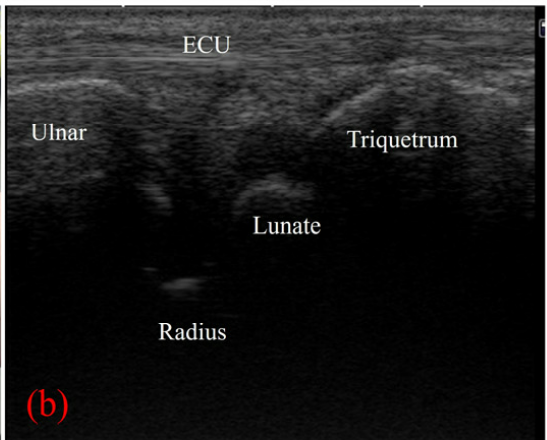

**'다이나믹 초음파'로 비교 분석하면서

두 가지 충격적인 사실을 알게 됐습니다.

@ https://doi.org/10.3390/s22010345